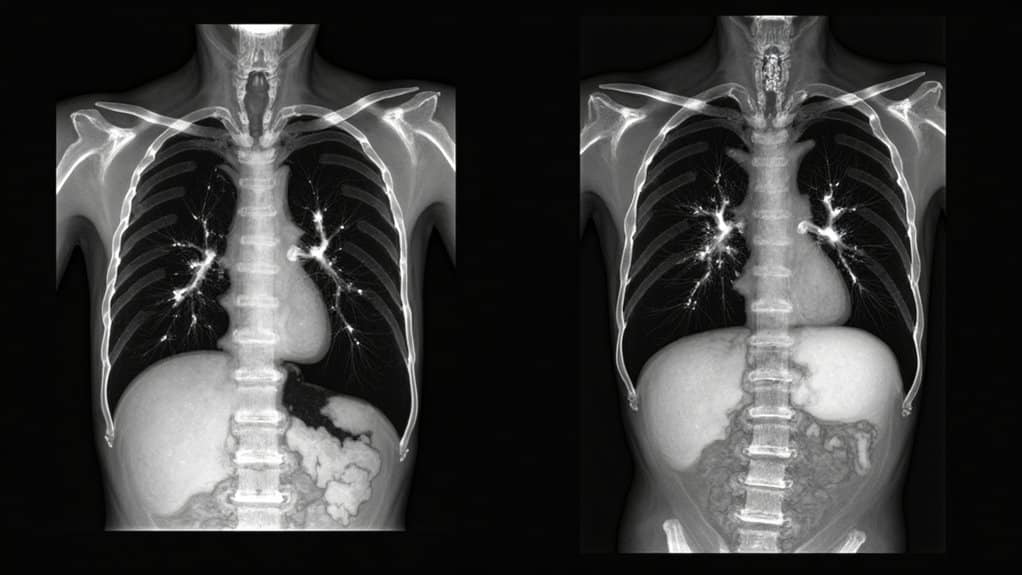

Doctors who’ve examined patients with crack lung symptoms report the lungs sound crackly, like someone crumpling up cellophane. In many diagnostic cases, a crack lung CT scan helps reveal how much damage has occurred and whether there are visible ground-glass opacities or scarring within the lungs.

To diagnose crack lung, CT scans and chest X-rays (CXR) are the fastest course of action for emergency departments, especially when the person is not honest about drug abuse. Crack lung CT scan and crack lung radiology images and crack lung CXR will show ground glass opacities (GGO), which appear like shattered or spun glass inside the lungs. GGOs show inflammation, fluid, puss, or scar tissue and help medical professionals figure out how severe the issue is and the best course of treatment.